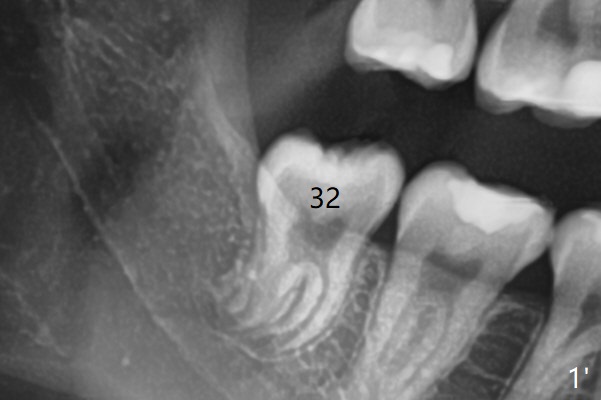

19岁女抱怨右下智齿远中龈下食物坎塞,不希望拔除,因为缺牙太多:先天性缺失一个下切牙,为了矫正又拔除4个双尖牙(图一)。临床检查32号牙远中牙龈覆盖(图二:*),而17号牙萌出不多(图三),没有食物坎塞史。局麻下,使用Diode Laser (Picasso)切除牙龈直到智齿远中咬合面暴露(图四)。术后突然意识到为了防止牙龈重新覆盖,必须做crown lengthening,也就是切除远中骨质(图五(黑色),与图一’对比),是吗?随访时利用Shining口扫记录,拍摄角度好。